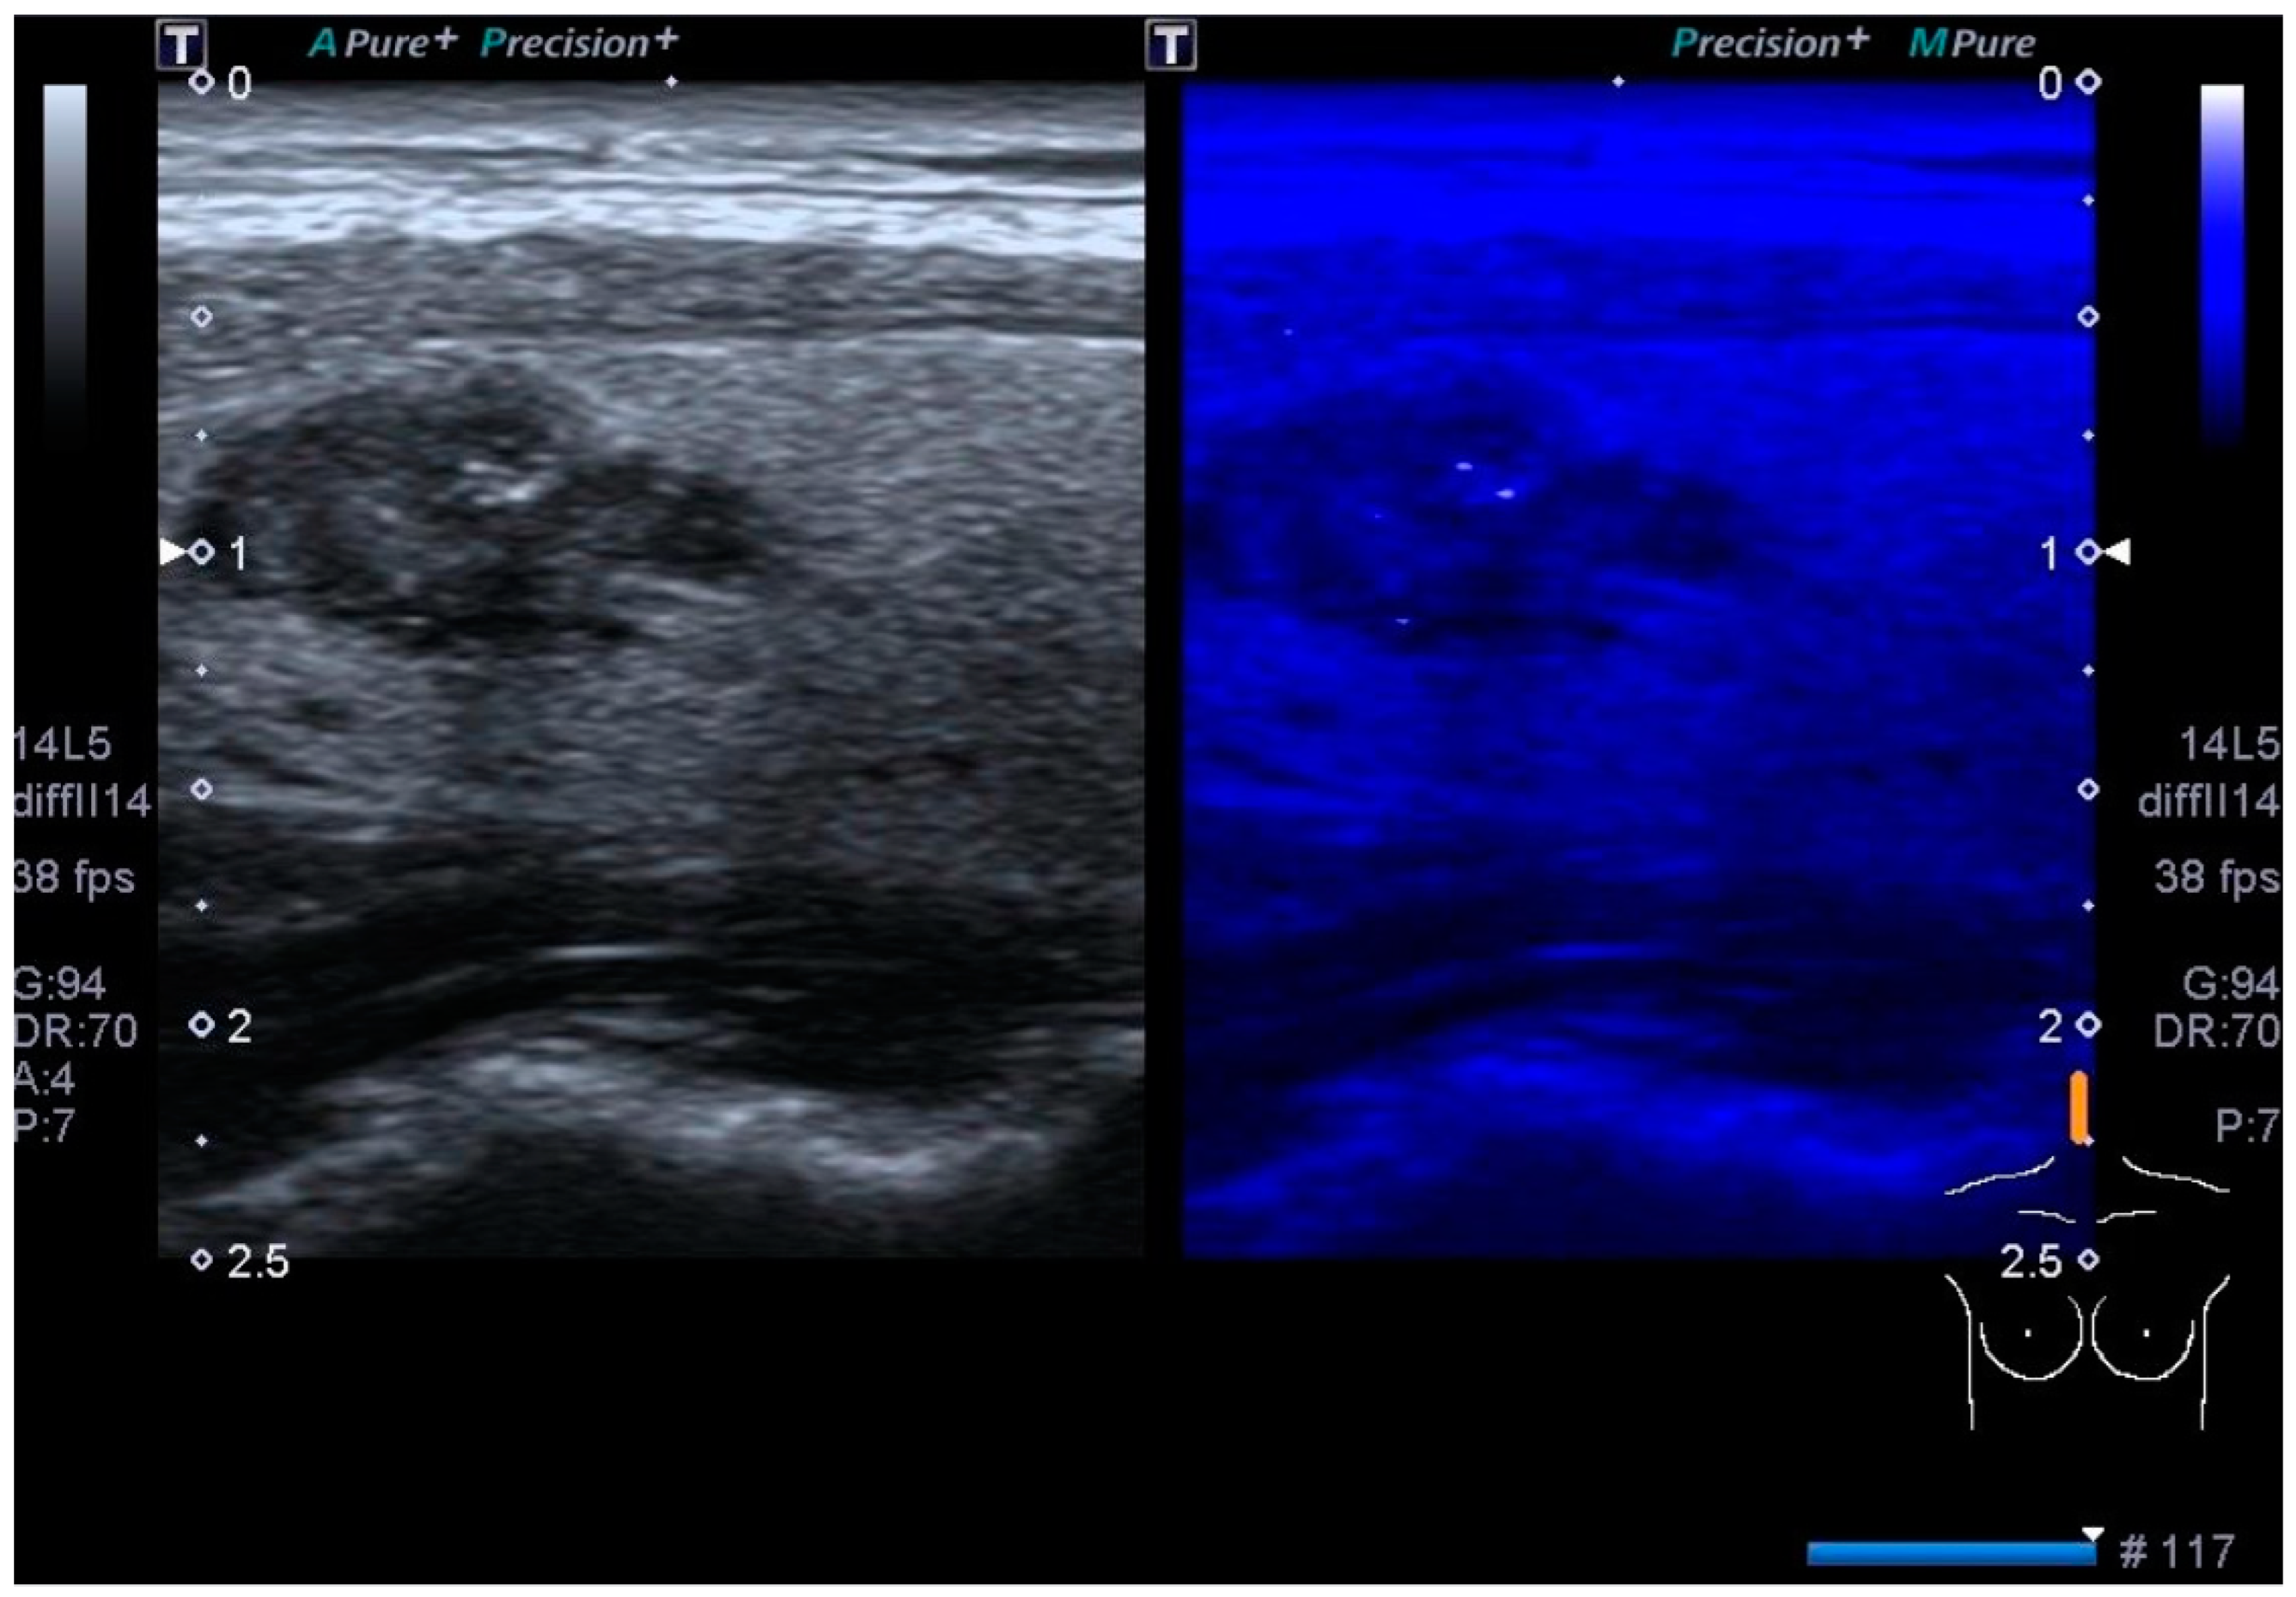

3.2. Color Doppler US

3.4. Elastography